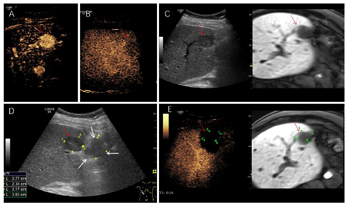

根据患者的实际情况,MDT讨论一致同意行超声引导下微波消融治疗。超声-MR融合成像提示共4个病灶复发。S8有2个邻近膈面病灶,为保护膈肌及保证视野清晰,行人工胸水、人工腹水辅助,因腹腔粘连较严重,膈下腹水操作失败,仅行人工胸水减少肺气对视野的影响,从而进行超声引导下消融、超声造影-MR融合成像评估效果(图1);S5小病灶邻近门脉且灰阶超声显示不清,应用超声-MR融合成像定位引导消融,并使用超声造影复查效果(图2);S5大病灶邻近胃肠道,因腹腔粘连行人工腹水操作较困难,改为使用球囊隔离技术将肝肿瘤与肠道分离,在保证肠道安全的情况下行超声引导下消融,并行超声造影-MR融合成像评估效果(图3)。

本例患者75岁,乙肝病史30年,自2010年检出HCC并手术切除后,近十年来多次复发,行血管介入、消融、手术切除等综合治疗,再次外科手术困难。2021年9月影像学发现肿瘤复发,其中,S5大病灶邻近胃肠道,S5小病灶邻近门脉,S8两个病灶邻近膈面。MDT讨论考虑患者曾行多次腹部手术,腹腔粘连严重,结合患者年龄较大等因素,一致决定行微创治疗—超声引导下微波消融。而该患者复发病灶均位于高危部位,行超声引导下人工胸腹水操作,并通过超声-MR融合成像导航定位、引导消融、超声造影复查效果,特别是使用球囊隔离技术将肝脏与肠道分离,以避免消融过程中产生的热量损伤胃肠道。术后复查超声造影提示4个病灶均消融完全。